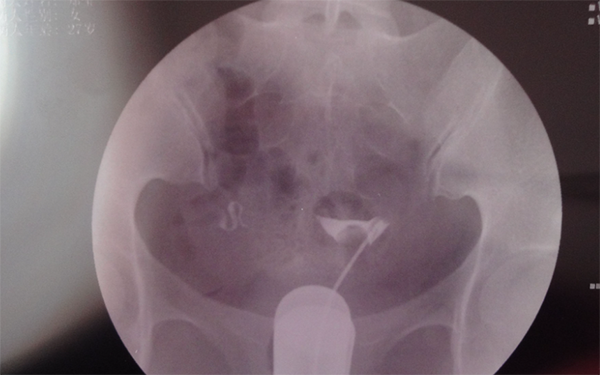

输卵管造影指的是医生使用专业的器械,通过阴道宫腔向输卵管内注入造影剂,可在影像学监测下,通过造影剂在输卵管内流动情况,可以明确了解输卵管是否存在问题,是不孕不育常见的检查方法之一,但输卵管造影对女性确实存在有一定的危害,以至于不能立即怀孕,具体如下: